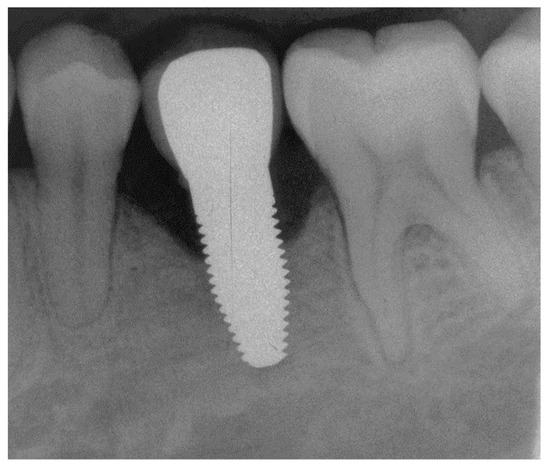

Appendix B. Exemplary Photographs and Radiographs from a Patient at Different Examination Time Points and a More Negative Outcome

Patient B:

Figure A15.

Radiograph of the perimplant bone situation before crown cementation.